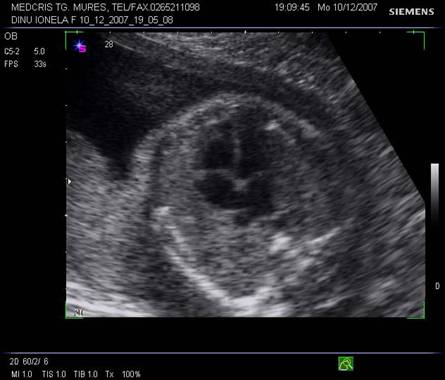

Fig. nr. 178. Planul 2 de sectiune a cordului cu aspectul inimii in 5 camere, emergenta aortei se adauga celor 4.